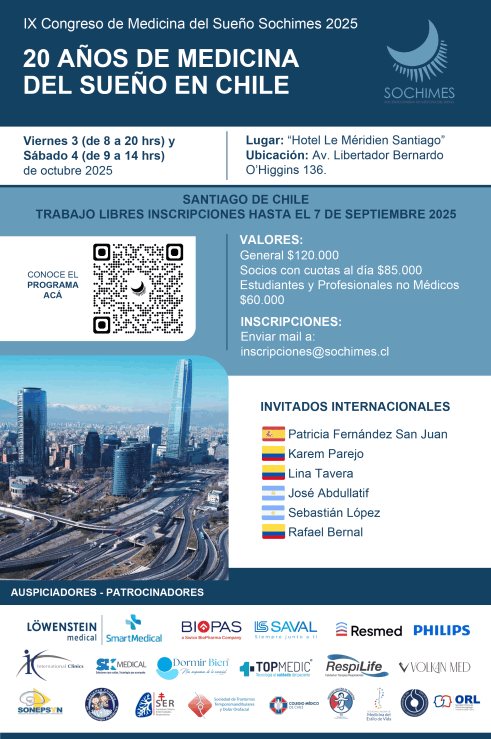

IX Congreso de Medicina del Sueño

20 AÑOS DE MEDICINADEL SUEÑO EN CHILE

03 y 04 de Octubre 2025

Hotel Le Méridien Santiago

05 y 06 de Septiembre de 2025

Hotel Le Méridien Santiago

-------------------------

03 y 04 de Octubre de 2025

Más Información >

- 16 Conferencias

- 06 Talleres

- 27 Expertos nacionales e internacionales.